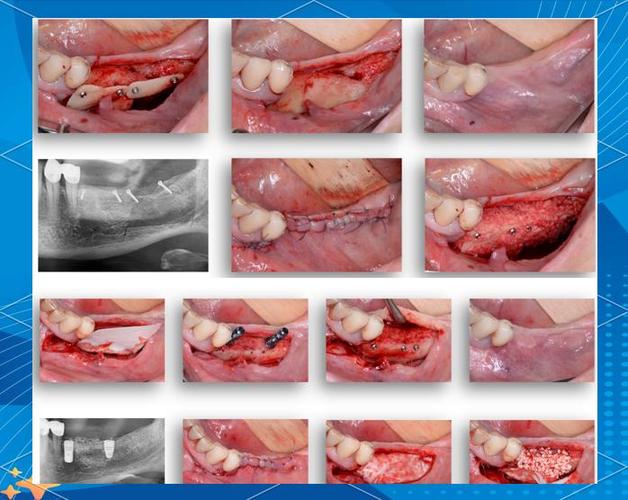

牙槽骨是支撑种植体的“地基”,若骨高度、宽度或密度不足,种植体易松动、脱落,甚至引发感染,骨粉的主要作用是填补骨缺损,引导成骨细胞附着、增殖,促进新骨形成,最终实现“骨结合”(种植体与自体骨融合),临床常用的骨粉包括自体骨(患者自身取骨)、异种骨(如牛骨、猪骨,经脱蛋白处理)、人工合成骨(如羟基磷灰石、磷酸三钙)等,其中异种骨因来源充足、成本较低,应用较广,但需确保其生物相容性和无免疫原性。

- 骨粉吸收与新骨形成:异种骨粉在植入后2-4周开始被巨噬细胞、成骨细胞分解,同时自体骨细胞在骨粉表面沉积,形成新骨,这一过程缓慢,通常3-6个月通过CT检查可见骨粉被新骨替代,密度接近自体骨。

骨粉吸收过多或移位

- 症状:植骨区高度、宽度不足,种植体植入后松动;或骨粉移位至邻近组织(如下颌管、上颌窦),导致麻木、鼻塞等。

- 原因:骨粉质量不佳(如孔隙率低,不利于细胞附着)、植骨区血液供应不足、或术后过早咀嚼硬物。

- 处理:若吸收过多导致骨量不足,需二次植骨;骨粉移位者需通过手术取出,并修复受损组织。

伤口裂开或骨粉暴露

- 症状:牙龈切口裂开,骨粉外露,呈白色或颗粒状,可能伴疼痛、出血。

- 原因:术后咬合创伤、口腔清洁不当(如用力刷牙、漱口过猛)、或缝合不牢固。

- 处理:小范围暴露可进行口腔消毒(如氯己含漱液),避免感染;若裂开较大,需重新缝合,必要时取出暴露的骨粉。